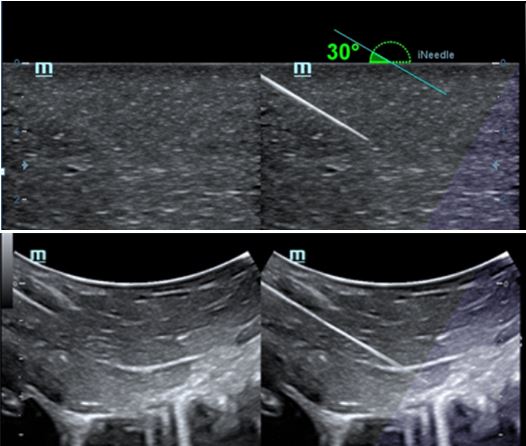

Режим на прецизно визуализиране на биопсионната игла. Изключително полезен особено при дълбока биопсия: позволява корекции на линията на сканиране, за да се постигне по-добра видимост както на иглата, така и на нервите и малките съдове и да се намали до минимум вероятността за увреждането на околните тъкани при манипулации.